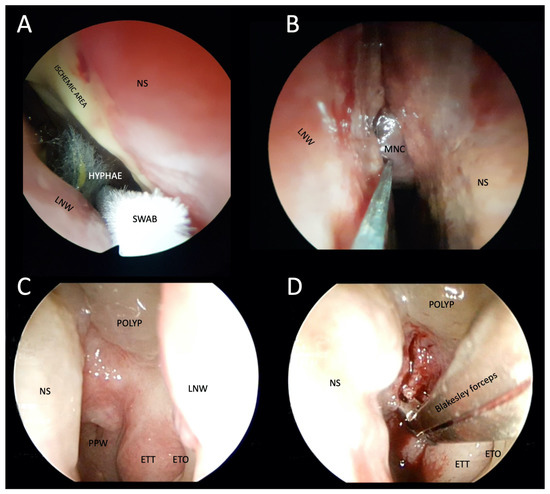

Figure 5.

Photographs of transnasal endoscopic collection of pus and tissue specimens for microbiological and histopathological examination in patients with suspected atypical skull-base osteomyelitis. (A,B) Swabs were taken from a patient with rhino-orbital-cerebral mucormycosis. Fungal hyphae are visible in the right nasal cavity, ischemia of the nasal septum, and the middle nasal concha necrosis, which has a blackish appearance (i.e., black turbinate sign). (C) Thickened epipharyngeal tissue with normal mucosa in a patient with atypical fungal skull-base osteomyelitis. (D) Deep biopsy after epipharyngeal incision. LNW: lateral nasal wall; NS: nasal septum; MNS: middle nasal concha; PPW: posterior pharyngeal wall; ETT: eustachian tube torus; ETO: eustachian tube orifice.